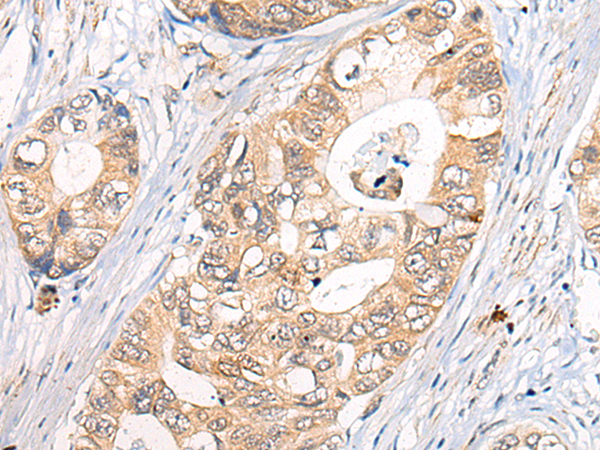

分类: 科研抗体货号: P02471别名: OSM; C7orf22; PP10187应用: IHC反应种属: Human